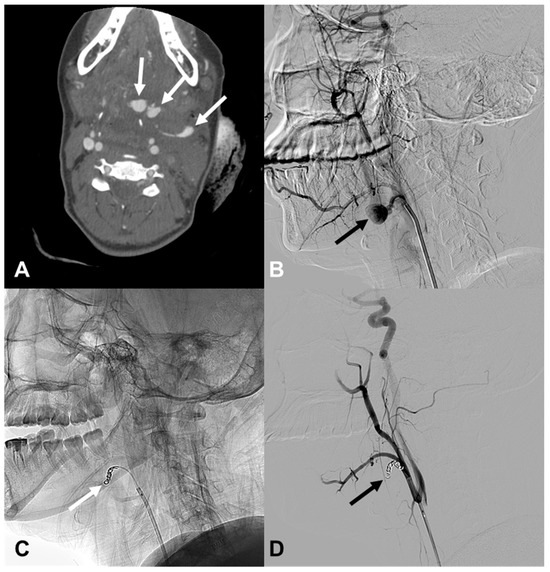

| 12 | 47/M | Stab | Arrest | R CCA-IJV fistula | EV, R distal CCA | cStent | Death 12 h d/t hypovolemic shock |

| 13 | 53/F | Stab | Bleeding | Hematoma, L neck | EV, L VA (V2) | Coil, bStent | Stable 1416 d F/U |

| 15 | 34/F | Stab | Bleeding | EV, R ICA | EV, R cervical ICA | cStent | Stable 45 d F/U |

| 16 | 32/M | Iatrogenic | Massive bleeding during surgery | NA | EV, R proximal CCA | cStent | Stable 2344 d F/U |